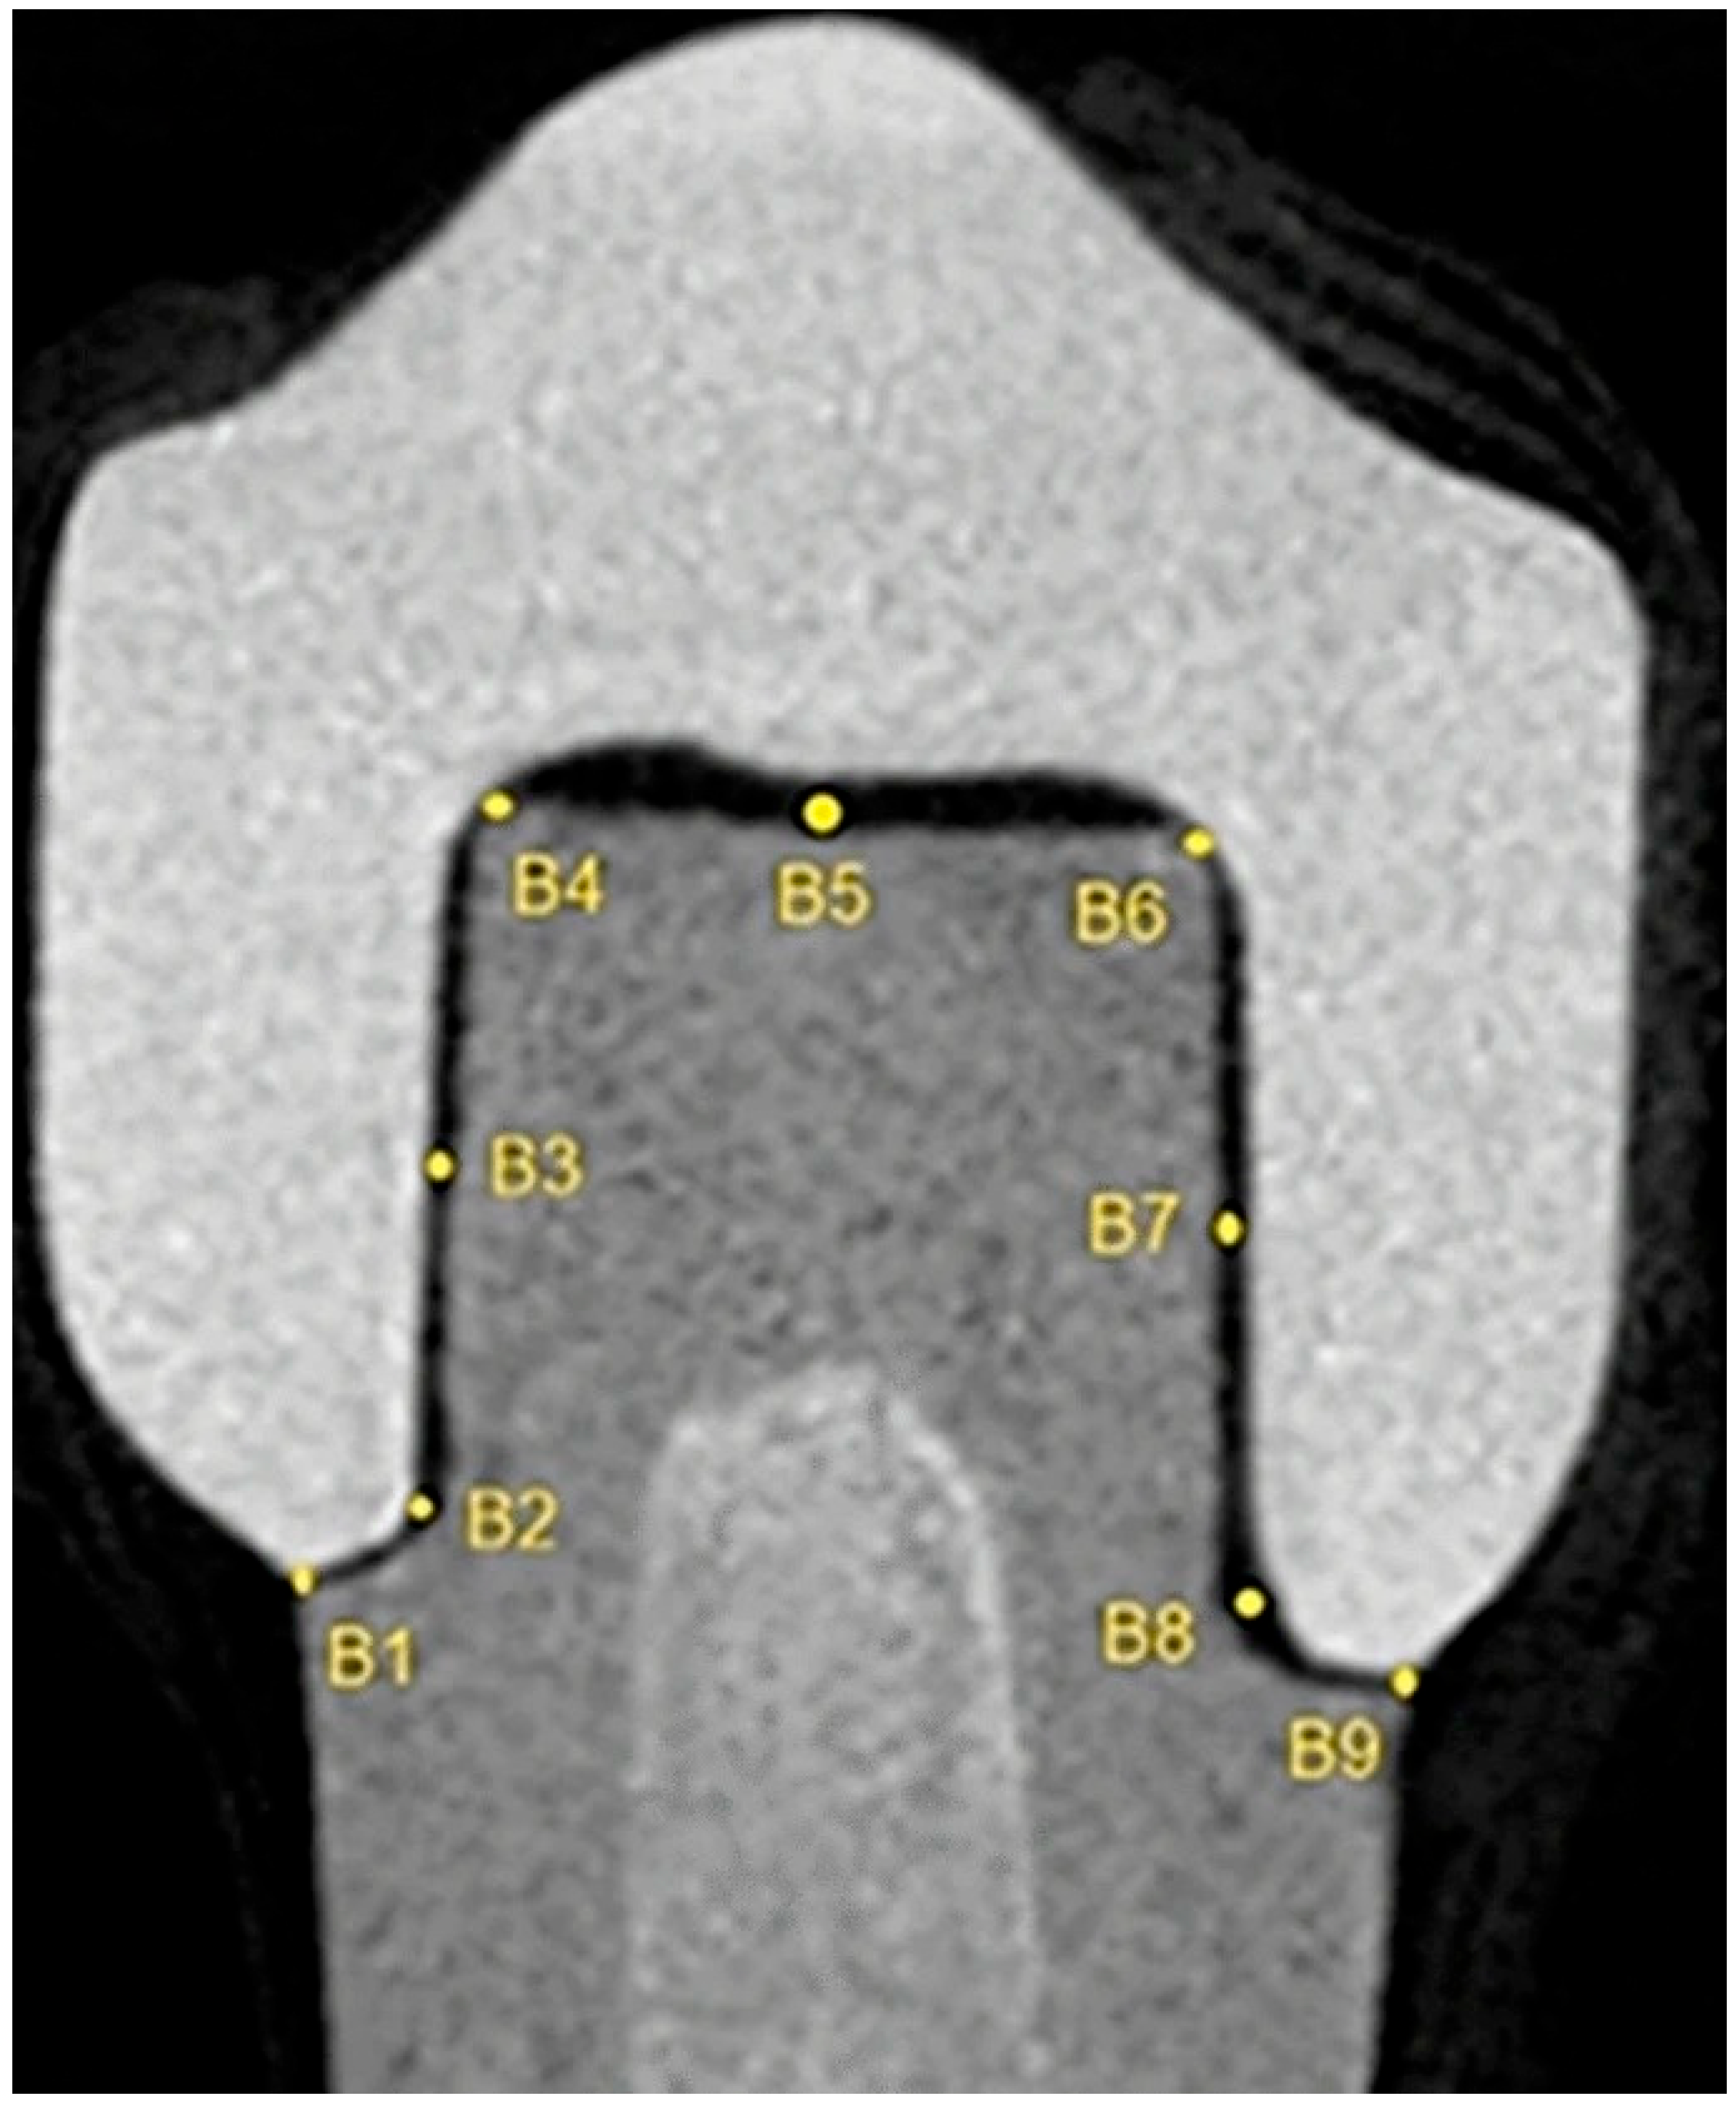

2.1. Linear Measurements